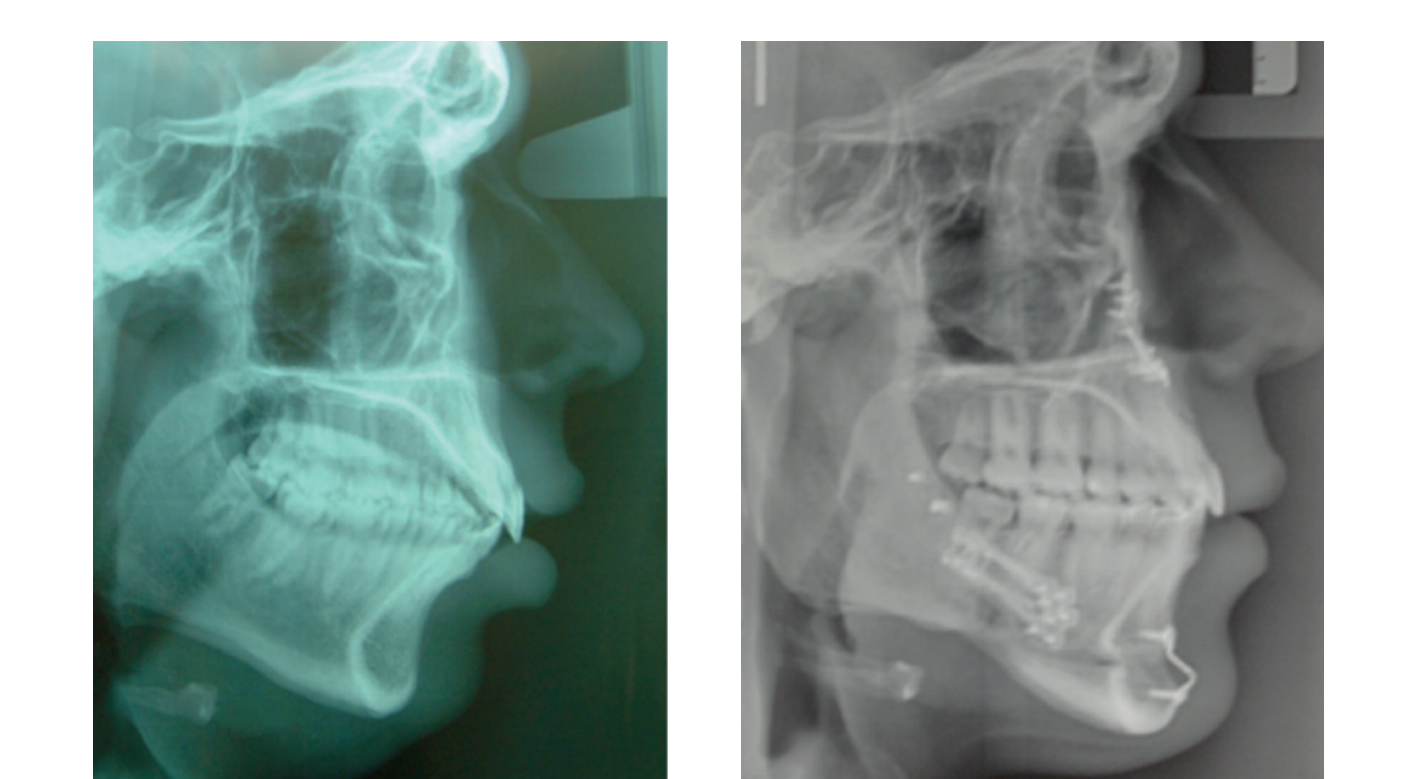

Скелетная экспансия привела к улучшению дыхательных путей, как показано на радиологических наложениях.

Лица с умеренной деформацией трансформируют свою эстетику, и улучшения выходят за рамки, поскольку нет другой техники, сравнимой с ортогнатической хирургией, которая вызывает изменения в дыхательных путях, как бимаксиллярная хирургия с изменением окклюзионной плоскости. У этого пациента операция вызвала скелетное расширение.